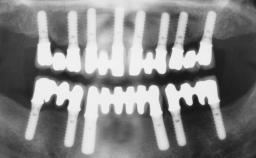

Immediate Loading of Six Implants in the Maxilla and Final Restoration with a Full-Arch Gold/Ceramic FDP Involving the Concept of Tilted Implants

# of Implants 6

Type of Implants One-Piece|Reduced-Diameter

Bone Augmentation Horizontal|Simultaneous